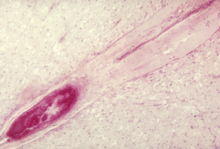

In around 1% of infections, poliovirus spreads along certain nerve fiber pathways, preferentially replicating in and destroying motor neurons within the spinal cord, brain stem, or motor cortex. This leads to the development of paralytic poliomyelitis, the various forms of which (spinal, bulbar, and bulbospinal) vary only with the amount of neuronal damage and inflammation that occurs, and the region of the CNS affected.

The destruction of neuronal cells produces lesions within the spinal ganglia; these may also occur in the reticular formation, vestibular nuclei, cerebellar vermis, and deep cerebellar nuclei.[36] Inflammation associated with nerve cell destruction often alters the color and appearance of the gray matter in the spinal column, causing it to appear reddish and swollen.[13] Other destructive changes associated with paralytic disease occur in the forebrain region, specifically the hypothalamus and thalamus.[36] The molecular mechanisms by which poliovirus causes paralytic disease are poorly understood.

Spinal polio

Spinal polio, the most common form of paralytic poliomyelitis, results from viral invasion of the motor neurons of the anterior horn cells, or the ventral (front) grey matter section in the spinal column, which are responsible for movement of the muscles, including those of the trunk, limbs, and the intercostal muscles.[15] Virus invasion causes inflammation of the nerve cells, leading to damage or destruction of motor neuron ganglia. When spinal neurons die, Wallerian degeneration takes place, leading to weakness of those muscles formerly innervated by the now-dead neurons.[41] With the destruction of nerve cells, the muscles no longer receive signals from the brain or spinal cord; without nerve stimulation, the muscles atrophy, becoming weak, floppy and poorly controlled, and finally completely paralyzed.[15] Maximum paralysis progresses rapidly (two to four days), and usually involves fever and muscle pain. Deep tendon reflexes are also affected, and are typically absent or diminished; sensation (the ability to feel) in the paralyzed limbs, however, is not affected.[42]